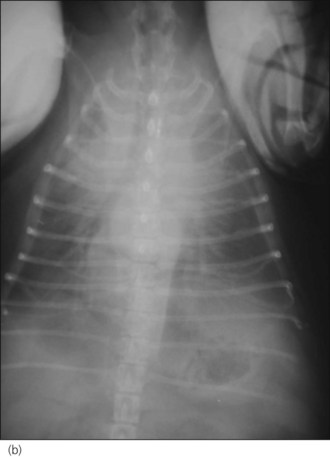

One hour later the dog’s respiration had improved to some extent and he had also urinated. As he was compliant, thoracic radiographs were performed with flow-by oxygen supplementation throughout (Figure 31.1). These findings were consistent with the suspected diagnosis of decompensated left-sided CHF secondary to probable mitral valve insufficiency but there was also evidence of right-sided heart failure.

Figure 31.1 (a) Right lateral and (b) dorsoventral thoracic radiographs of a dog with end-stage mitral valve disease showing cardiomegaly with left atrial enlargement and dorsal displacement of the caudal part of the trachea, an alveolar lung pattern affecting mainly the cranial lung lobes with air bronchograms, mild bilateral pleural effusion and hepatomegaly.